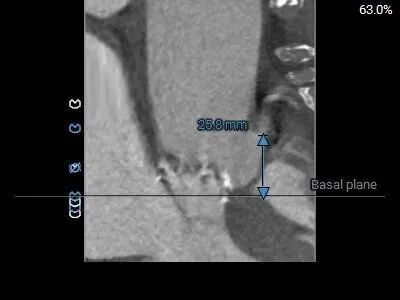

左冠19.4,右冠25.8,综合分析冠脉阻挡风险适中

•主动脉瓣水平夹角约74°,严重横位心,主动脉弓宽度角度可,弓顶部有钙化分布,